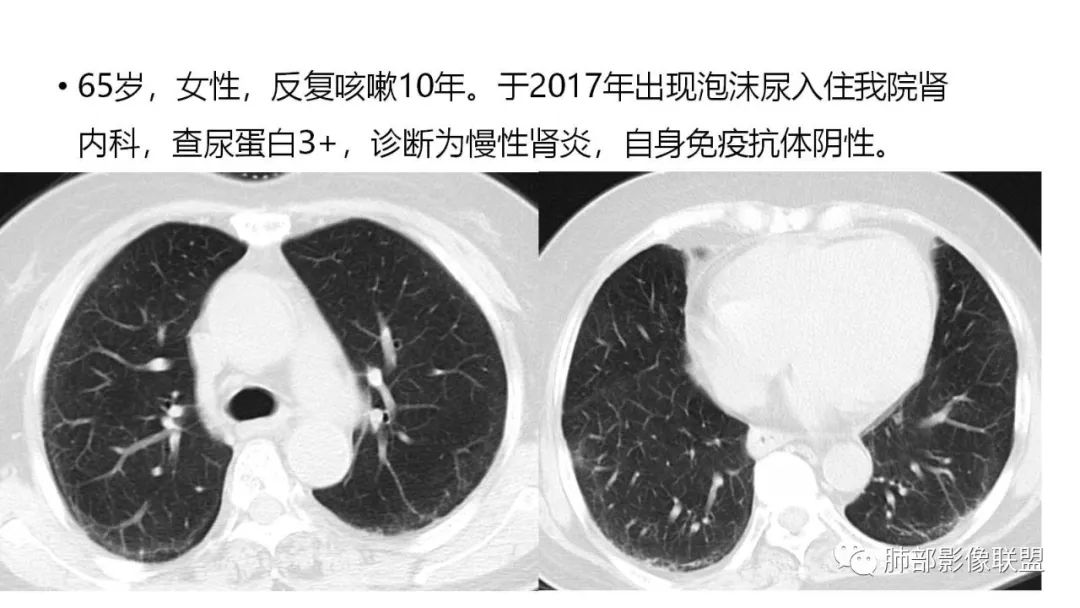

三、本例是一个误诊多年的病例,给我们很多启示:

1.多学科探讨的重要性:肾内科忽视肺部病变,后续需要呼吸、影像、病理共同探讨。

2.粘液腺癌易伪装成肺炎的形态,尤其是当患者本身具有免疫色彩的时候,易误诊为间质性肺炎,或肺部感染。若治疗无效,取得病理很重要。

3.粘液腺癌常常因为标本不够,病理无法诊断,影像诊断很重要,取病理方案很重要。甚至多次取病理。

4.回到本例,左下肺病变两次好转,均未经过肿瘤治疗,第一次是支气管镜后,第二次是当其他病变都在进展的情况下,左下肺病变范围反而缩小趋于浅淡。